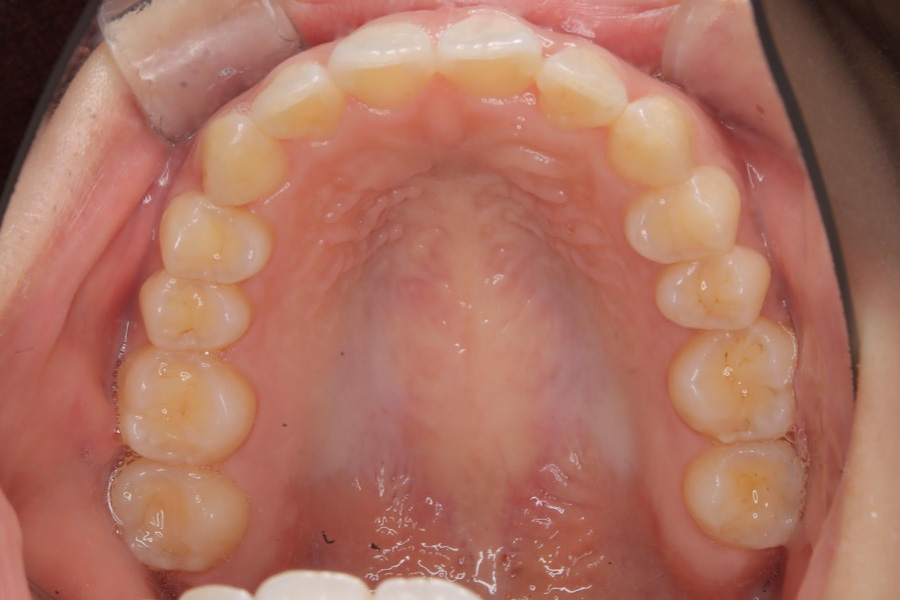

【20代女性】

全体のガタつきを

インビザライン矯正で治療したケース

治療後

主訴 全体のガタつきが気になる

治療内容 インビザライン矯正

非抜歯